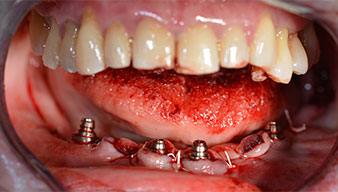

È stata eseguita una tomografia computerizzata Dentale Cone Beam in 3D (CBCT, con Planmeca) per aiutare la programmazione dell'intervento e la riduzione di rischi. L'esame ha evidenziato che la qualità e quantità dell'osso disponibile era sufficiente per eseguire l'intervento e la ricostruzione immediata, utilizzando il metodo Fast & Fixed. In base al protocollo del sistema, gli impianti sono stati inseriti in posizione 35, 32, 42 e 45. Gli impianti distali vengono installati a un angolo massimo di 45 gradi. Così facendo, il profilo che ne risulta viene spostato in posizione posteriore, generando un poligono di supporto più ampio (Fig. 3).

Dopo aver rimosso la dentatura residua dalla mandibola, la cresta alveolare viene esposta da 37 a 47.

Prima di tutto, è stato individuato il forame mentoniero come limite della struttura anatomica. Successivamente, l'osso corticale della cresta è stato lisciato con un manipolo e una fresa larga a rosetta (Fig. 4).

È stato avvitato un moncone angolato di 35 gradi per compensare la divergenza degli impianti distali. Ne risulta un profilo globale degli impianti situato il più perpendicolare possibile al piano occlusale. Questa situazione è un prerequisito per il posizionamento occlusale di protesi provvisorie e, successivamente, di quelle definitive (Fig. 15 e 16).

Successivamente, sono state prese le impronte e il morso di costruzione della paziente, per consentire al tecnico dentale di iniziare a realizzare la ricostruzione provvisoria. Quest'ultima è stata innestata lo stesso giorno (Fig. 17 e 18).